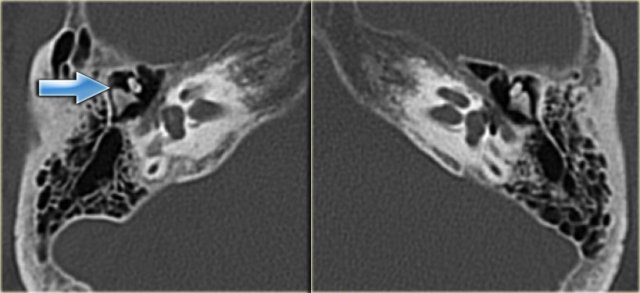

On the left images of a man who had suffered a traumatic head injury two months previously.

He complained of intermittent tinnitus.

There is a longitudinal fracture (yellow arrow) coursing through the mastoid towards the region of the geniculate ganglion.

There is a dislocation of the incus with luxation of the incudo-mallear and incudo-stapedial joint (blue arrow).

No involvement of the inner ear.

Left ear for comparison.